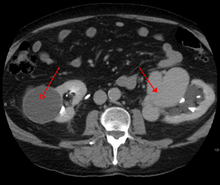

AVMs can occur in various parts of the body:

- kidney[8]